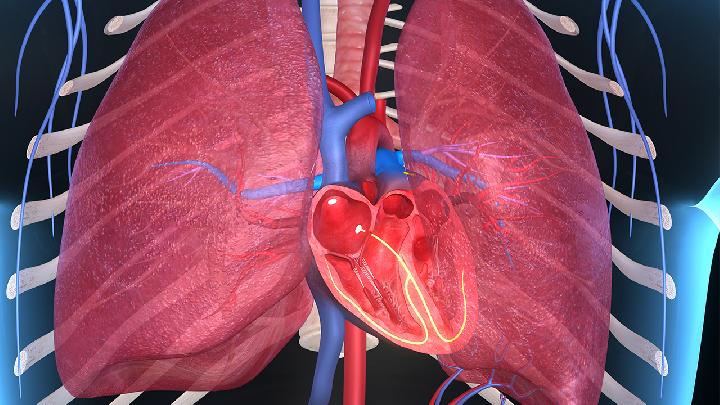

宝宝出生后100天左右(3-5个月)时,免疫力降至最低点。这时,宝宝会很容易遭受疾病的干扰,而肺炎就是其中之一。根据相关统计数据,发展中国家每年有超过1亿5千万的5岁以下儿童患肺炎,全球每年超过150万的儿童因为肺炎失去生命。而在我国5岁以下儿童死亡病例中,肺炎是第二位死因,其中重症肺炎中约50%源于肺炎链球菌感染。

我们在生活中可能都很少听说过房间隔缺损这样的疾病,此病对于我们的生活工作,影响是非常大的,若不能及时的解决,麻烦更是会接踵而至。尤其是如果小孩子患上这个问题,那种后果就更加让人担忧了。那么宝宝房间隔缺损会导致死亡吗?